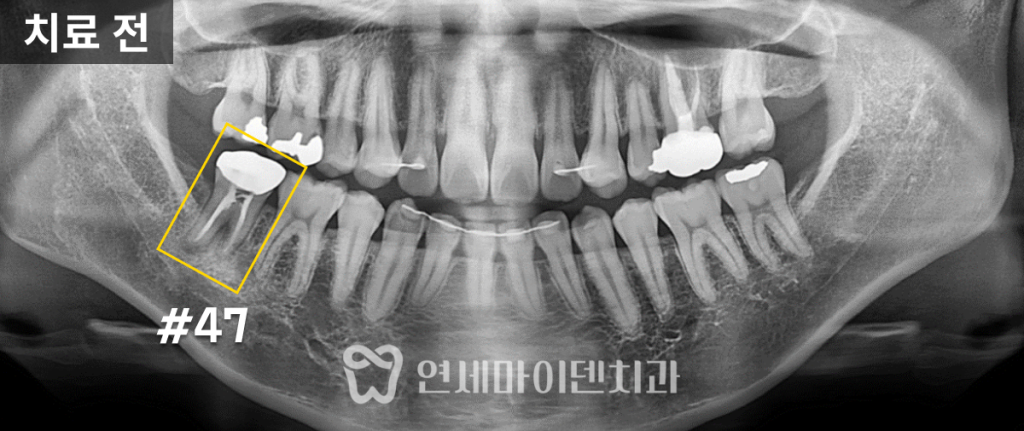

환자분은 오른쪽 어금니 부위의

지속적인 통증과 잇몸 염증으로 내원하셨습니다.

수년간 잇몸이 붓고 가라앉기를 반복했고,

통증이 턱 쪽까지 번지는 상태였습니다.

육안으로 보기에도 잇몸 염증이 심한 상태였습니다.

잇몸 염증은 치아의 뿌리 끝이 아닌

치아 중간 부위에서 심하게 발생해 있었고,

이런 형태의 염증은 치근단염보다

예후가 좋지 않은 경우가 많습니다.

수술 부위는 하치조신경관과 매우 가까웠으며,

뿌리 크랙으로 인해 뼈 흡수가 많이 진행된 상태였습니다.

이에 3D 네비게이션 CT 분석을 통해

정확한 식립 위치와 각도를 미리 계산했습니다.